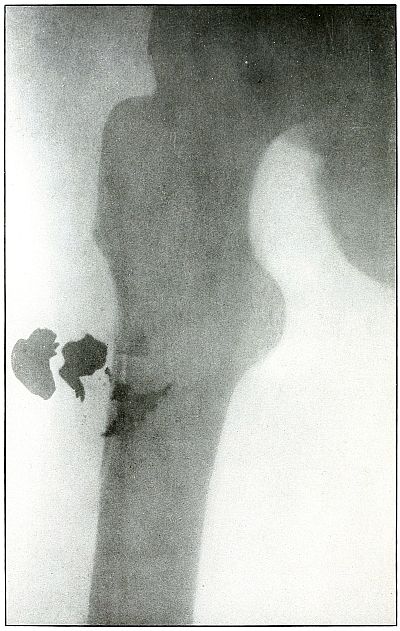

Plate 56.

[Pg 123]

Rifle—Plate 56.

LOWER EXTREMITY.

Gunshot Fracture Below the Middle of the Femur,

with Lodgment of the Bullet Near the Fracture.

The course of the projectile was transverse. The long splitting

fracture, with few large fragments and the lodged undeformed missile,

indicate that the injury to the bone was caused by the missile

striking the bone with large cross section or at an inclined angle so

that all of the remaining energy of the projectile at long range was

absorbed by the bone.

Had the point of the ball struck the bone with the same energy, it

would have produced smaller fragments and might then have passed

beyond the bone. The normal size of the diameter, slightly shortened

length, greater density of the point of the shadow, shows the bullet

to lie behind the bone with its nose pointing slightly backward. The

actual length of the bullet is 1.25 inches: the length of the shadow

is 1 inch.

Treatment and results would be about the same as in

plates 49 and 50.